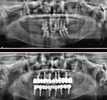

Implant tedavisi